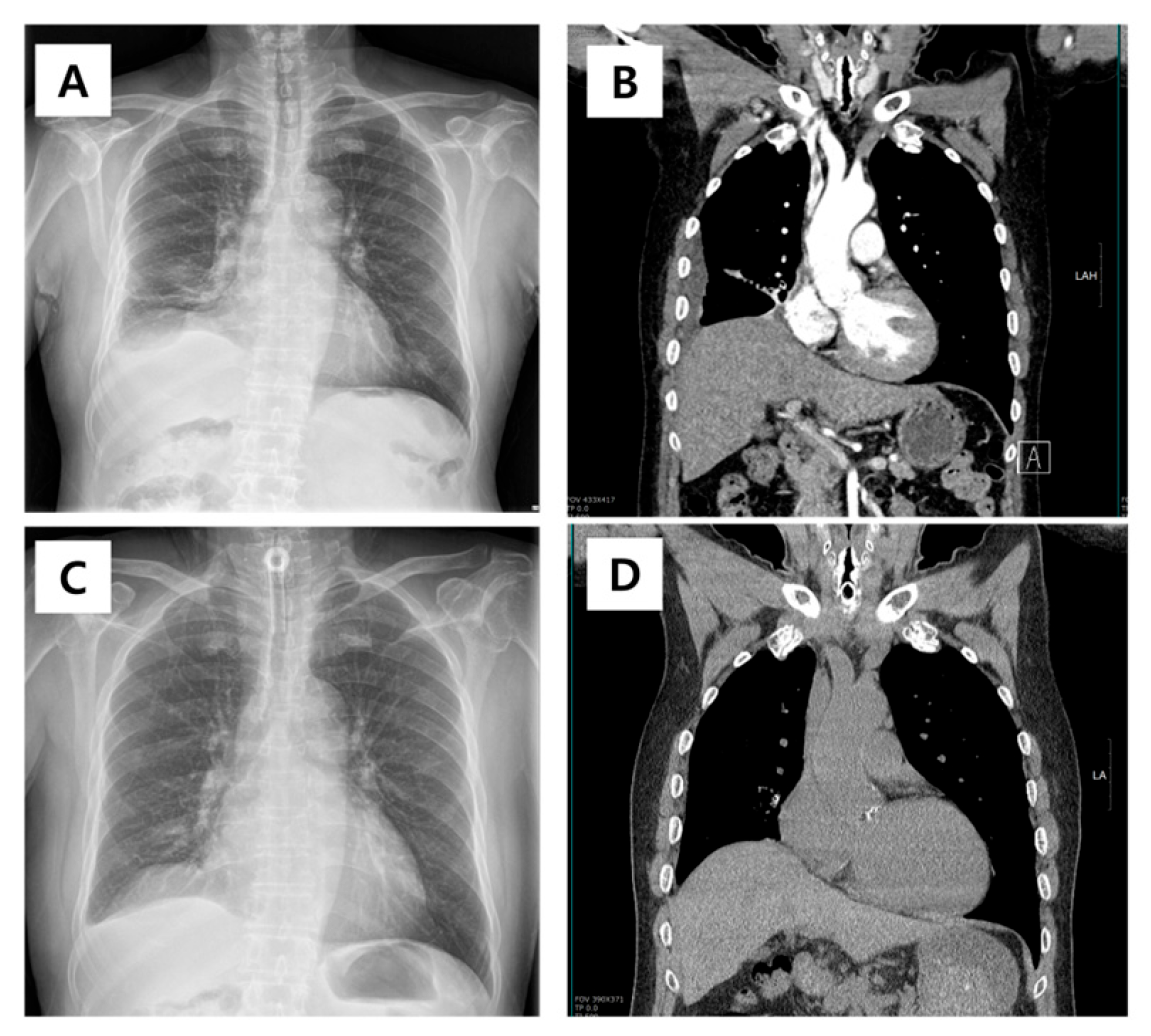

| Danckers (2015) | 27-year-old male | Acute hypercapnic respiratory failure; subglottic mass with cystic and solid component obstructing 75% of the airway | Intubation, mechanical ventilation; surgical drainage; prophylactic tracheostomy; antibiotics | Asymptomatic after tracheostomy removal; persistent vocal cord fixation | [6] |